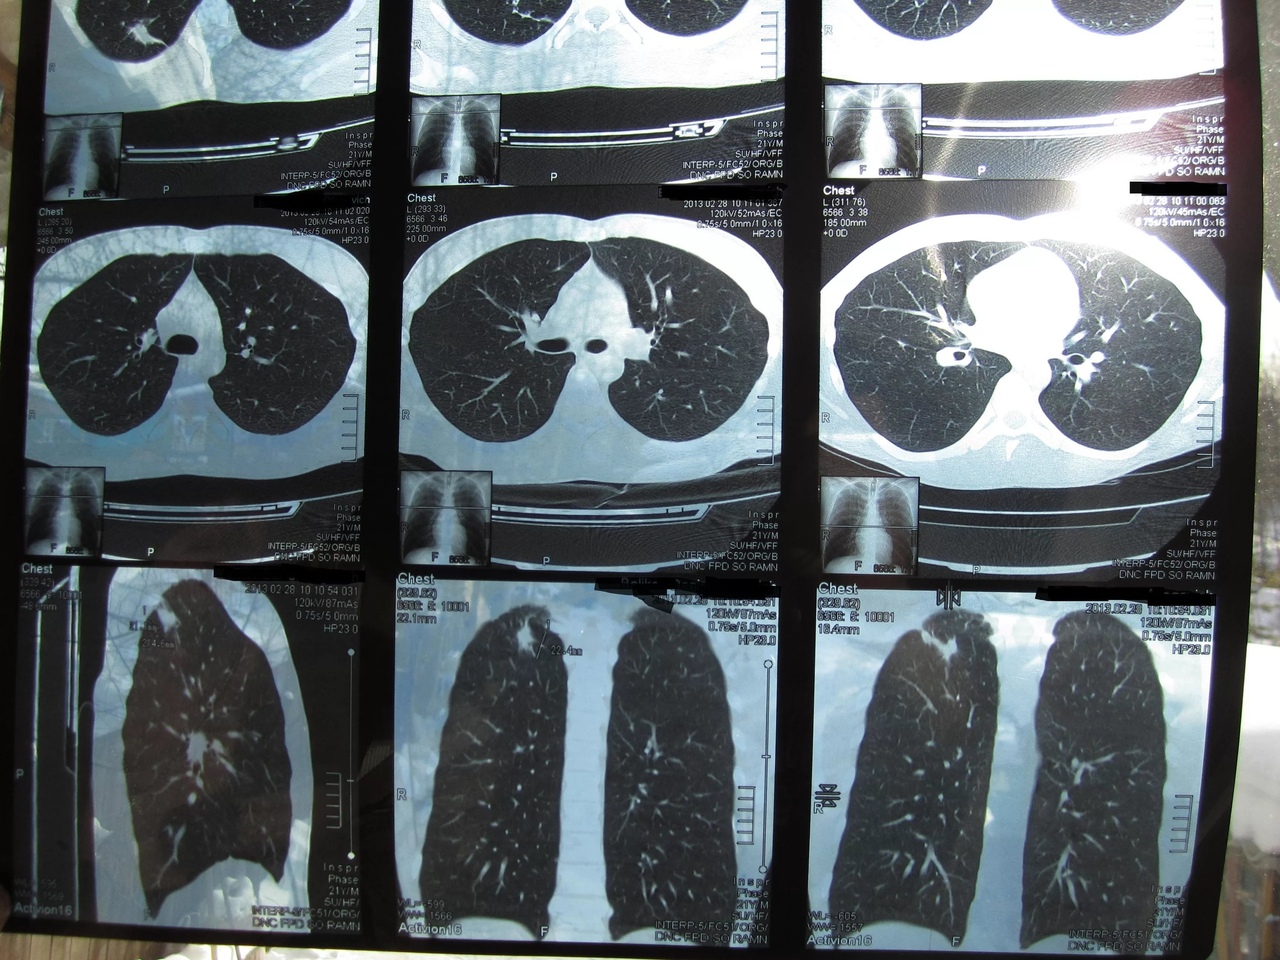

Снимок легких при туберкулезе является важным методом диагностики этого заболевания. На рентгеновских снимках можно увидеть изменения в легких, которые свойственны туберкулезу.

Кт лёгких при туберкулёзе

Инфильтративный туберкулез легких кт

В данной статье представлены многочисленные фотографии снимков легких при туберкулезе, чтобы помочь вам понять, как выглядят изменения легких на рентгеновских снимках при этом заболевании.